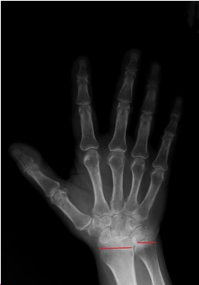

The radius and ulna are connected by the dorsal and volar radioulnar ligaments and are expected to be in a neutral position relative to each other within the wrist joint.[4] Ulnar variance is a term used to describe the positional relationship between the distal ulna and radius. Negative ulnar variance is the presence of the ulna 1 mm or more proximal to the radius and has been associated with conditions such as ulnar impingement syndrome, scapholunate dissociation, and Kienböck’s disease (Figure 1). Positive ulnar variance is the presence of the ulna 1 mm or more distal to the radius and is associated with conditions such as ulnar impaction syndrome, cartilaginous tears in the carpal bones, early degenerative changes, and triangular fibrocartilaginous complex (TFCC) tear (Figure 2).[5]

Hand and wrist radiographs were evaluated blindly by 2 rheumatologists (MP-SK). Hand radiographs were analyzed according to the Modified Sharp Score (MSS) system.7 The presence of any erosion or joint space narrowing (JSN) was used as a criterion to define “RA-type joint involvement (RJI).” “Severe joint involvement (SJI)” was defined as the presence of erosion with a score of 3 or higher or JSN with a score of 4 or more according to the MSS. Patients were also evaluated for ankylosis of any hand joint. Ulnar variance, as described by Hulten, was determined by measuring the distance between horizontal lines drawn at the subchondral bone of the distal radius, just beneath the articular cartilage, and the most distal subchondral border of the ulnar head.[8] A displacement of 1 mm or more of the ulna relative to the radius was defined as AUV. Radiographic evaluation was performed with full agreement; if there was disagreement between the readers, the X-ray was re-evaluated and an agreed final decision was made.